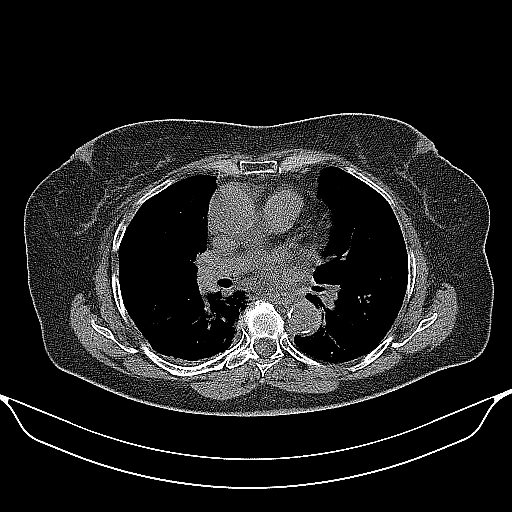

Image Grid

4Γ—3 grid: Rows show different image types (Original NATIVE, Reconstructed NATIVE, Original VENOUS, Generated VENOUS), Columns show windowing techniques (No Window, Lung Window, Mediastinum Window)

Original NATIVE CT scan (input)

No window - Raw intensity values

Reconstructed NATIVE CT scan (cycle consistency)

Original VENOUS CT scan

Generated VENOUS CT scan (A→B translation)